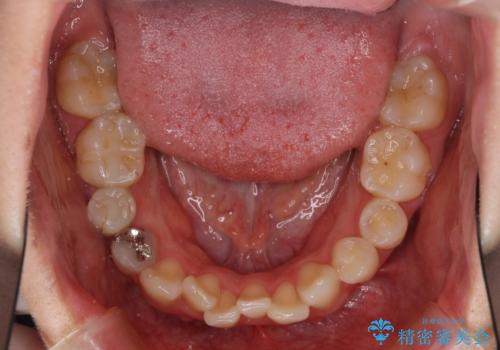

上下の骨幅を改善したことで、スムーズに歯列矯正を行うことができました。

奥歯の咬み合わせを改善する必要があったため、治療は長期化しましたが、きっちりと仕上げることができました。